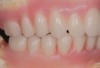

Fig 19. Patient smile shown 3 years post-treatment.

Figure 19

Fig 20. Patient intraoral condition 3 years following delivery of maxillary and mandibular All-on-4 definitive prosthesis.

Figure 20

Dental rehabilitation with the All-on-4 treatment concept is often a life-changing event for edentulous and terminal dentition patients that results in unprecedented quality of life improvements (Figure 17 through Figure 20).